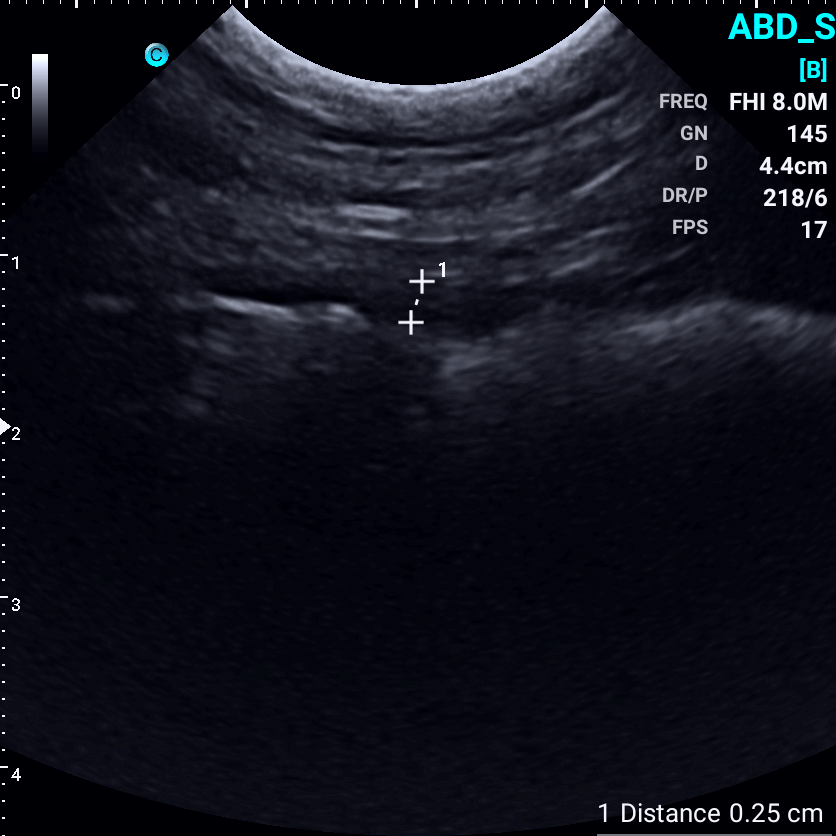

Images from the Sonoeye P6